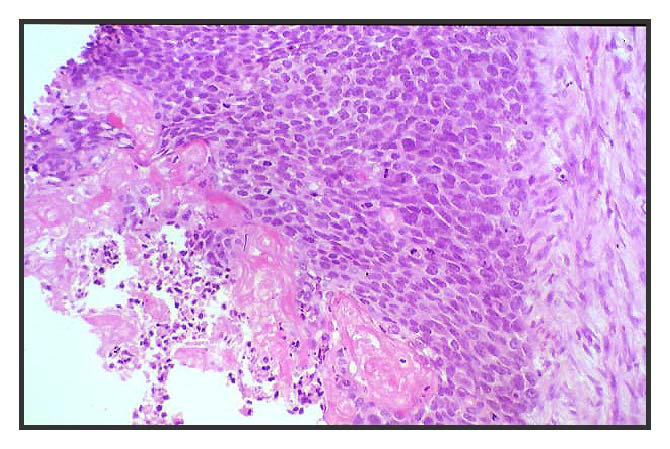

Figura 4: Alta densidad celular y moderada atipia citológica. Alto índice mitósico ( 47/10 campos de gran aumento ).